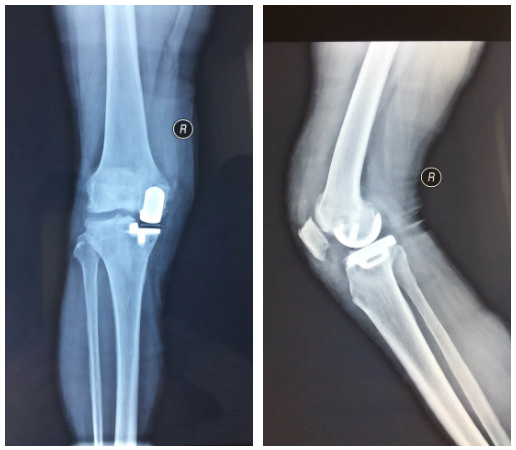

單踝置換

膝關(guān)節(jié)置換

嚴(yán)重膝關(guān)節(jié)疾病導(dǎo)致全膝破壞的終極治療是膝關(guān)節(jié)置換,骨二科采用內(nèi)軸膝系統(tǒng),能更好的模擬膝關(guān)節(jié)的正?;顒?,完美恢復(fù)膝關(guān)節(jié)的功能,達(dá)到Forget knee的效果。